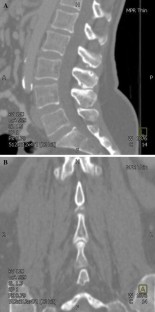

200 abdominal CT scans taken for trauma and vascular investigation were reformatted to allow precise bony measurement of the lumbar spine. Two observers were blinded from the age and demographics of the patients. Sagittal and coronal plane projections were used to measure the height and width of the spinous processes (L1–L5), respectively. The relationship between spinous process size, age, and supine lordosis was investigated.

Fig. 2